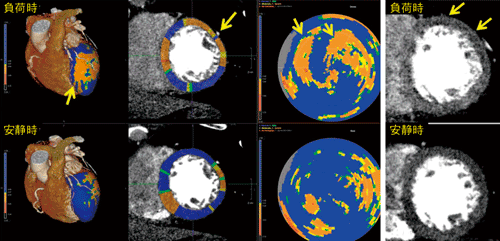

“CT Myocardial Perfusion”アプリケーションは,安静時および負荷時における同じ造影位相の心臓画像から,左心室心筋の血流状態について,虚血部位と周辺の健常部位とを比較評価することを目的としている。対象データが読み込まれると,2分程度でtransmural perfusion ratio3)等のperfusionに関するパラメータが計算される。perfusion解析には,高精度な左心室心筋の輪郭検出精度が求められるが,CT Myocardial Perfusionでは,全自動で必要な精度での心軸抽出と心筋輪郭検出が行われる。後述の冠動脈解析(CT Cardiac Coronary Analysis)と併用することで,形態と機能の両面から心臓を評価できる強力な機能である。

図1に解析例を示す。負荷時において,左心室心筋短軸像の前壁の広い領域に,安静時には見られなかった低CT値の領域が見られる。Polar Map表示においても同様に,負荷時に顕著な虚血を示す領域が存在する。冠動脈を確認すると,この領域の支配血管である左冠動脈に狭窄および高度な石灰化が認められ,虚血との対応を把握することができる。また,VR画像上にCT心筋perfusion結果をフュージョン表示することができ,より責任血管の同定がしやすくなっている。

図1 CT Myocardial Perfusion解析例:左冠動脈狭窄症例

(画像ご提供:相澤病院様)